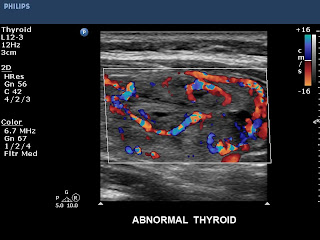

Varis hastalığında kan kaçağı (reflü) sonucu oluşan varislerin çoğu çıplak gözle görülebilir; bunlar buzdağının görünen kısmını oluştururlar. Ancak kapak yetmezliği sonucu varise neden olan damar ya da damarlar, yani olayın esas nedeni çıplak gözle görülemez ya da elle yapılan muayene ile anlaşılamaz. Buzdağının görünmeyen kısmını oluşturan bu damarlar ancak “renkli Doppler ultrasonografi” denen özel bir ultrason cihazıyla görülebilir.

Bu cihazla ayrıca cildin alt kısımlarında yer alan ve çıplak gözle görülemeyen varisler ile bacağın atardamar ve derin toplardamar sistemi de görüntülenebilir. Bu nedenle her varis hastası mutlaka önce renkli Doppler ultrasonografi ile incelenmeli, hastalıklı damarların bir “haritası” çıkarılmalı ve tedavi bu haritaya göre yapılmalıdır. Renkli Doppler ultrasonografi mutlaka deneyimli bir hekim (tercihan radyolog) tarafından yapılmalıdır, çünkü varis hastalığında yanlış ya da yetersiz tedavilerin en önemli nedeni renkli Doppler ultrasonografi tetkikinin yanlış yapılması ya da yorumlanmasıdır .

TİROİD RENKLİ DOPPLER